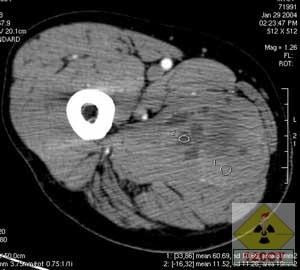

X線示左股部軟組織富血供性占位。鏡下所見:腫瘤細胞呈腺泡樣巢狀排列,瘤細胞大小不等,巢內緣不整,外周較圓滑,巢與巢之間為豐富的、互相連通的血管網。瘤細胞圓形、卵圓形或多角形,界清,胞漿豐富,有嗜酸性顆粒,核圓形,異型性小,含有核仁,核分裂象不易找到。

好發於青春,女性多見,常位於四肢深部肌肉或筋膜,少數可見於腹壁、肛旁區、舌、腹膜後、頸背部。腫瘤生長緩慢,早期無痛,常偶然發現,大者直徑可達6~10cm。瘤塊雖增大不快,但血循豐富,淺表者可觸及搏動,包括轉移至皮下,直徑1cm大小腫瘤,搏動也很顯著,部分病人可發生廣泛的血循轉移,主要轉移至肺、骨、腦、皮下等部位,少數有淋巴轉移,轉移至骨者,沿骨長軸發展境界清楚溶骨性破壞,無骨膜反應,酷似某些骨轉移癌的表現。